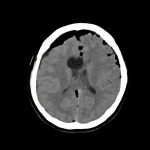

症例 '16年10月

No.

年_番号

手術年月

患者年齢

’16_145

'16年10月

40代

病名

術式

備考

脳室上衣腫

断層撮影

手術前

1

手術前2

手術後